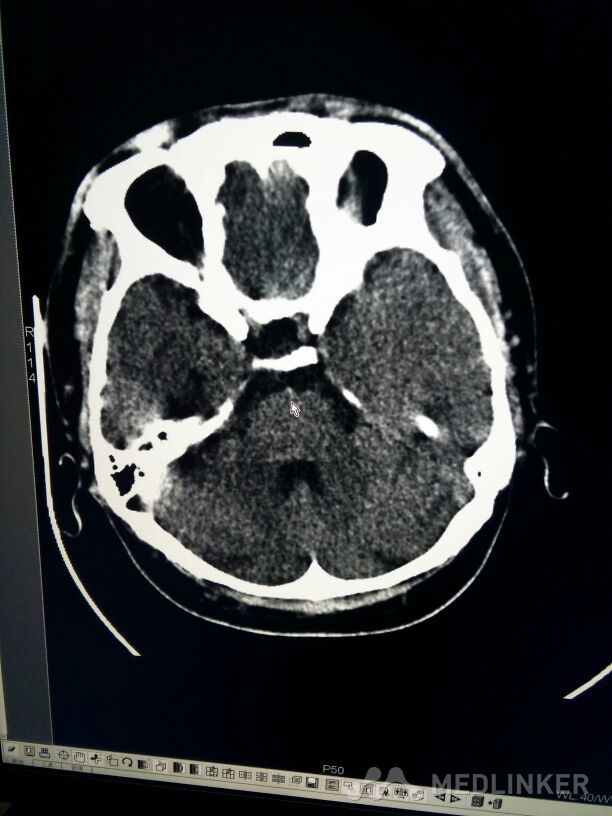

考虑表皮样囊肿?

放射科检查

表皮样囊肿

表皮样囊肿和皮样囊肿的影像学特点有哪些区别?